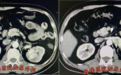

正当李先生和家人松了一口气的时候,最近的一次复查显示了肿瘤复发的迹象,而且出现了肾静脉癌栓。癌栓在肾静脉内快速生长,已到达肠系膜上动脉水平。再次手术需面临腹腔肠管粘连、肾动静脉粘连、癌栓脱落等等难关,手术风险极大。

复发肾脏肿瘤及左肾静脉癌栓,癌栓已达肠系膜上动脉水平。